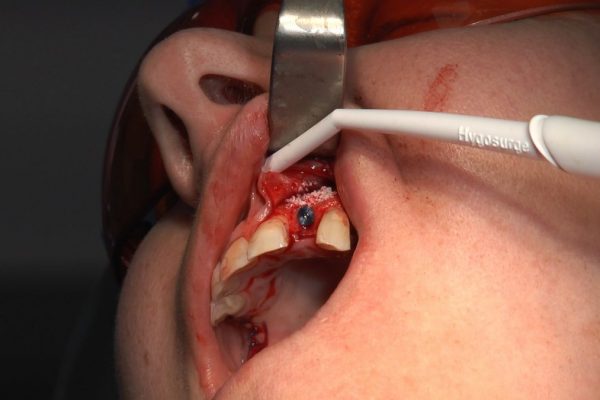

W ostatni weekend czerwca 2018 roku kursanci II Sezonu Preludium Implantologii odbyli piątą, finałową sesję, która w całości podporządkowana była praktyce. W ciągu dwóch dni zabiegowych Lekarze uczestniczący w szkoleniu przeprowadzili szereg zabiegów pod kierunkiem dr n.med. Violetty Szycik. Wszczepili 17 implantów oraz przeprowadzili ekstrakcje i zabiegi regeneracyjne kości. Zabiegi były wykonywane także w sedacji dożylnej z udziałem specjalisty anestezjologii i intensywnej terapii dr Jolanty Grzybowskiej. Preludium implantologii to nowy program edukacyjny dla adeptów implantologii stomatologicznej, którego celem jest wprowadzenie do implantologii poprzez pozyskanie wiedzy w szerokim zakresie i uwzględnieniem szczegółów mających decydujące znaczenie dla powodzenia leczenia implantologicznego. Ale tak jak wszystkie szkolenia w Instytucie Vivadental, w tym wiodące Practiculum Implantologii, zorientowane jest na praktyce i samodzielnym wykonywaniu zabiegów pod kierunkiem Mentora. To najlepsza edukacja w medycynie zabiegowej, a zarazem najlepszy start do implantologii.